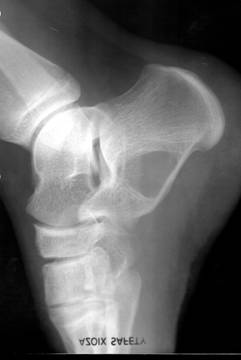

b)   Tumora cu mieloplaxe (celule gigante) – se intalneste exclusiv la adulti, afectand mai ales femeile. Are sediu epifizar, predilect langa genunchi si realizeaza o imagine transparenta, excentrica ce umfla osul. Imaginea descrisa are o structura neomogena data de travee opace ce dau un aspect de fagure tumorii. Corticala este impinsa in afara si subtiata. Trecerea intre tumora si diafiza sanatoasa are loc brusc, dand compactei un aspect amputat

Fig. 84 – Tumora cu mieloplaxe